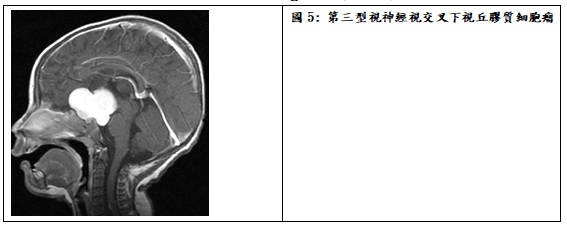

依據Dodge分類法從位置來區分,視神經路徑膠質瘤可分為第一型:僅位於視神經,第二型:位於視交叉或沿伸到視神經,第三型:視交叉延伸到視徑、下視丘及鄰近腦室(圖5)。位於前兩型的視神經膠質瘤,顯然會先有眼震、斜視、或單側眼球突出或視力減退的表現,而若腫瘤位置延伸到下視丘,還可能會有內分泌賀爾蒙的失調,如生長遲滯、性早熟或青春期延遲。視神經膠質瘤也常見於第一型神經纖維瘤病症的病患,因此對於初診病童也應要一併篩檢有無此腫瘤。大多數視神經膠質瘤的病理分級是第一或二級星狀細胞瘤,所以臨床症狀的進展較緩慢,腫瘤經長期的追蹤也常維持穩定,因此治療的策略以保持視力及相關神經功能為主要考量,對於腫瘤體積不大且視力仍保留的病童,建議第一線先以化學藥物控制,如果腫瘤體積很大或導致阻塞性水腦,或在化療中仍繼續進展時,則考慮先以手術清除部分腫瘤再根據病理分級,加上後續的輔助化療。手術的目的主要是確定病理診斷、減少腫瘤體積或處理腦脊髓液阻塞,但仍有可能需要放置腦室內引流管解決水腦症。僅少數可能是第三級以上膠質瘤時,才需要採合併放射線照射與化療的方式。